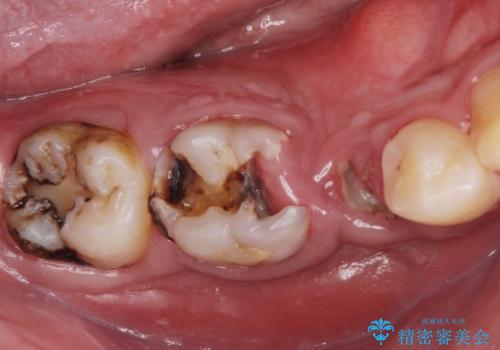

- 口の中をマスク生活の間に全て治したい、見た目を良くしたいとの事で来院。

まず徹底的に虫歯を取り除き、保存が出来ない部位は抜歯(親知らずを含む)を行い、根管治療が必要な部位は精密根管治療を行いました。